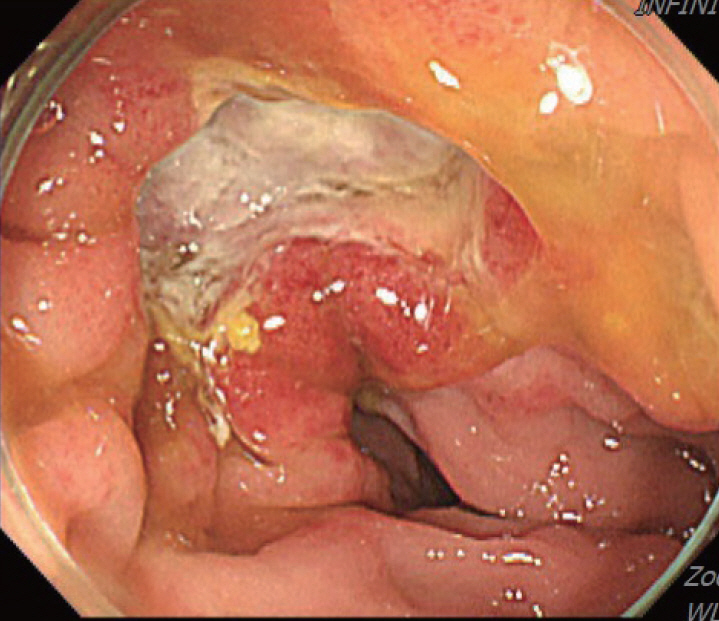

A 70-year-old male underwent sigmoidoscopy after a routine computed tomography (CT) examination, which showed thickening of the sigmoid wall (Fig. 1). Sigmoidoscopy revealed a colonic ulcer, and a biopsy was performed. The lesion was identified as a tubular adenoma; therefore, the patient was referred to the gastroenterology department for repeat biopsy and additional tests. The patient’s medical history included high blood pressure and alcoholic hepatitis. His social history showed that he drank 0.5-1.0 bottle of soju daily and was never a smoker. Information regarding his family history was excluded from the study. The patient had no gastrointestinal symptoms such as abdominal pain or diarrhea, and physical examination findings were unremarkable. Although the biopsy showed a tubular adenoma, the initial colonoscopy indicated that the gross margin of the ulcer was irregularly shaped (Fig. 2), raising suspicion for malignancy. Therefore, despite being asymptomatic, the patient was informed, and another colonoscopy was performed 2 months later. The follow-up examination revealed a scarred sigmoid ulcer located 30 cm from the anal verge, which seemed to have improved compared with the previous findings. Re-biopsy demonstrated features consistent with a simple ulcer (Fig. 3). Accordingly, we concluded that this was a benign colonic ulcer with an inflammatory and ischemic cause rather than cancer, and a follow-up CT scan was sche-duled 1 month later. At the follow-up visit 1 month later, the patient complained of abdominal discomfort after eating for a week, which had not occurred before. He denied having fever, chills, nausea, or vomiting. A subsequent abdominal CT scan showed an approximately 9-cm cavitary lesion abutting the sigmoid colon and urinary bladder dome in the small intestine (Fig. 4). This was accompanied by diffuse nodular omentomesenteric infiltration and peritoneal thickening with small ascites. Based on these findings, the patient was suspected to have a malignant tumor, such as scirrhous carcinoma, inflammatory bowel disease, peritoneal carcinomatosis, or peritonitis, and was referred to a surgeon for surgical treatment. The patient was hospitalized immediately. On admission, the patient complained of abdominal discomfort after eating, and mild generalized abdominal tenderness was noted on physical examination. He was hemodynamically stable. Laboratory testing revealed high white blood cell count of 11.45 × 103/μL (normal range, 4.0-10.0 × 103/μL) with a differential of 67.6% neutrophils (normal range, 38.0-75.0), normal hemoglobin of 16.1 g/dL (normal range, 13.0-17.0), normal platelet count of 151 × 103/μL (normal range, 150-400 × 103/μL), and slightly elevated C-reactive protein level of 7.69 mg/L (normal range, 0.0-5.0). Serum electrolyte and kidney function test results were normal. On the 3rd day of hospitalization, the patient underwent laparoscopic small bowel resection. Immunohistochemical analysis of the resected tissue showed positive staining for CD3, CD4, CD8, CD56, and CAM 5.2 (epithelial marker), and a negative staining for CD10, CD20, CD21, and CD30 (Fig. 5). Histopathological evaluation revealed infiltration by small- to medium-sized T-cell with prominent epitheliotropism, consistent with MEITL. The final diagnosis was MEITL, involving the sigmoid colon, urinary bladder, and peritoneum. Postoperatively, the patient developed persistent ileus with progressive ab-dominal distension and loss of bowel passage, necessitating a second emergency surgery on the 20th day of hospitalization. On the 25th day of hospitalization, the Hemovac drainage became purulent, blood pressure decreased, and the patient went into shock; therefore, a third emergency surgery was performed under the suspicion of bowel perforation. On the 45th day of hospitalization, the patient died of refractory septic shock, presumed to be a complication of intestinal perforation.

Figure 3.

Colonoscopy showing a scarred sigmoid ulcer 30 cm from the anal verge, with apparent improvement compared to previous findings.